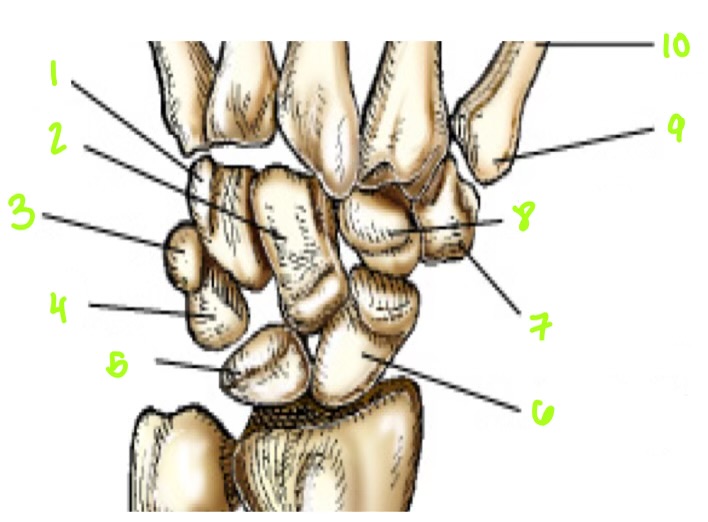

1

1

Hamate

2

2

Capitate

3

3

pisiform

4

9

Trapezoid

5

10

Trapezium

6

11

Scaphoid

7

14

Lunate

8

15

Triquetrum

9

16

Pisiform

10

17

Capitate

11

18

Hamate